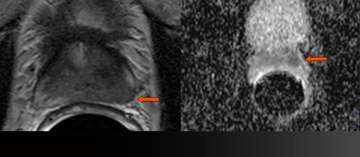

7) MR-Guided Targeted Biopsy

MR-Guided Targeted Biopsy

• 63 y/o, PSA 8.8 → 13.2 over 5 years

• All systematic biopsies negative

• Hypointense left anterior lesion with restricted diffusion is moderately suspicious, not in biopsy zone

• Read More >